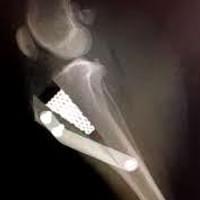

Chirurgia ortopedica

Nella nostra struttura si offre un servizio di chirurgia ortopedica tramite l’utilizzo di diverse tecniche operatorie, quali i fissatori esterni e l’utilizzo di placche e viti (fissazione interna), per il trattamento delle fratture .Per il trattamento della Rottura del legamento crociato craniale del ginocchio, si effettuano le metodiche piu’ moderne come: la TTA POROSA (tibial tuberosity advancement) e la TPLO (osteotomia livellante del piatto tibiale) .

Ci occupiamo anche delle patologie chirurgiche legate alla Displasia di rotula.